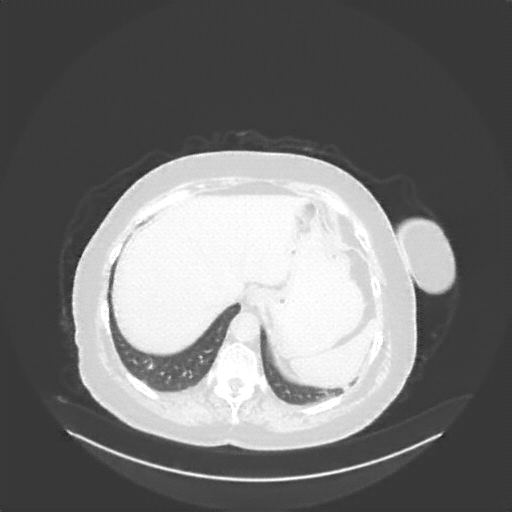

Generated VENOUS CT scan (A→B translation)

Full window (WL 1023.5, WW 4095 β†’ Low βˆ’1024, High +3071)

Lung window (WL -600, WW 1500 β†’ Low βˆ’1350, High +150)

Mediastinum window (WL 40, WW 400 β†’ Low βˆ’160, High +240)